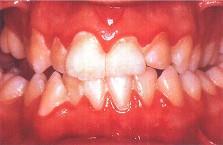

问题 下列哪项不是慢性龈缘炎的临床表现 ( )

选项 A.牙龈充血肿胀 B.探诊龈沟出血 C.龈沟深度超过3mm D.牙周附着丧失 E.无牙槽骨吸收

答案 D